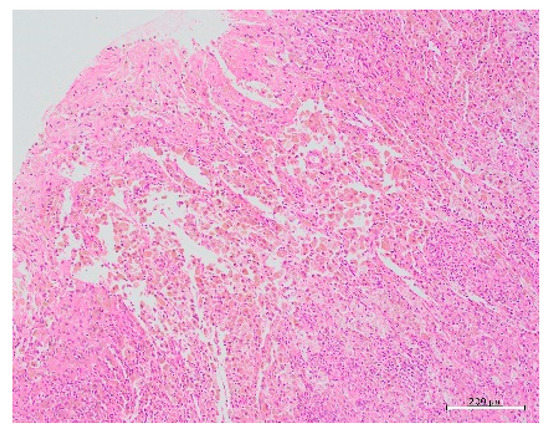

2. Case Presentation

| This case | 22 | 0 | 0 | 15 | 36 | L | 51.9 | None | CT, MRI: None | Laparoscopy | 3 cm, lateral, left side | Harmonic Scalpel, scissors forceps | 2 layers using 0 PDS | 14 | 69 | few | 2 | Present study |